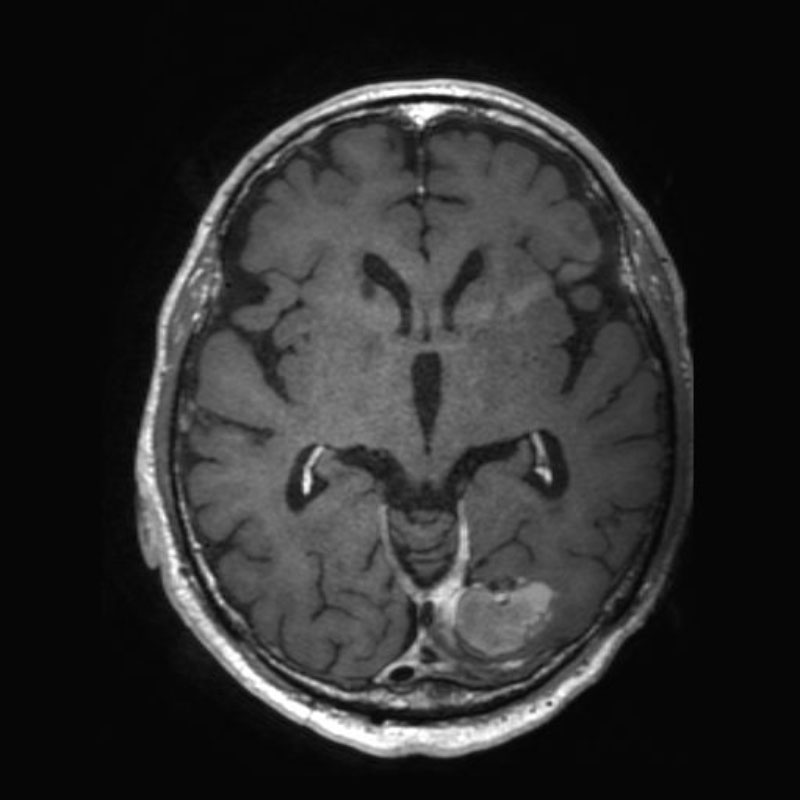

699

'25年11月

50代

左前頭葉腫瘍

頭蓋内腫瘍摘出術

No.’25_101 手術前1

No.’25_101 手術前2

No.’25_101 摘出 前

No.’25_101  摘出 中

No.’25_101 摘出 後